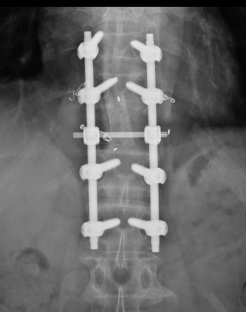

在困难面前,我院脊柱外三科团队没有退缩,在精心策划手术方案后,首先请介入科为老李做了节段血管栓塞,以减少术中出血,而后由陈海龙主任医师主刀,带领主治医师马俊杰、管床医师朱博组成的手术团队,在麻醉医师紧密配合下与全程神经监测保护下,细致分离神经血管,小心保护脊髓组织,成功完整地切除了病变椎体及附件,并应用人工椎体及脊柱钉棒系统重新建立脊柱稳定性,以便老李早期下地活动。在脊柱外三科团队的共同努力下,手术历经四个多小时,取得圆满成功,术中没有任何神经损伤症状出现,术后一周患者老李已经在支具保护下下床活动。